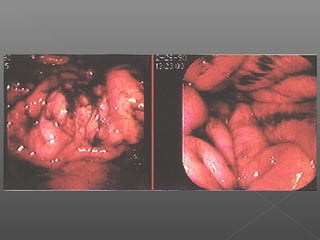

Angiodisplasias

Colitis isquemica

ANGIODISPLASIA CECAL

POLIPO SANGRANTE

CANCER DE COLON

COLITIS ULCEROSA CRONICA INESPECIFICA

SARCOMA DE KAPOSI

DIVERTICULOS SANGRANTES

PROCTITIS POSTRADIACION

ANGIODIPLASIA COLONICA